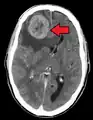

- Brain metastasis: neurological symptoms such as headaches,[10] seizures,[10] and vertigo[10]